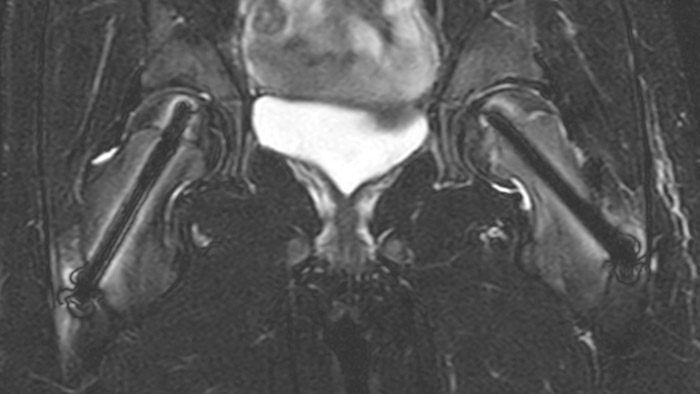

Perthes disease in left hip The affected area on the upper circumference of the left hip shows contrast uptake in the dynamic scan. The radial scan nicely depicts the hip area, despite the dark shape in the center that is inherent to the radial way of scanning.

After intervention with two cannulated titan screws, it is important to check that the circumference is normal and without necrosis. The screws can cause major metal artifacts, but O-MAR allows to improve visualization of tissue and bone in the near vicinity of MR Conditional orthopedic implants1. 1 Only for use with MR Safe or MR Conditional implants by strictly following the Instructions for Use